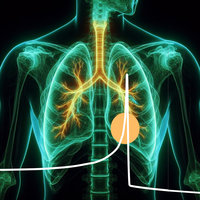

Biophysics & Tumor Therapy with Ion Beams